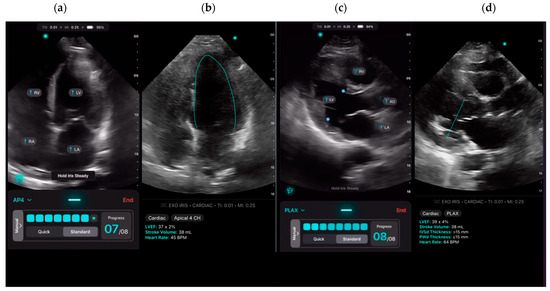

To assess the feasibility and inter-user reliability of the AI-assisted echo, we scanned a small cohort of patients (Cohort 1) multiple times. In these patients, the expert and all available novices separately and independently acquired their best attempts at PLAX and A4C views suitable for LVEF calculation using the AI-assisted tool on the Exo IRIS probe (Figure 1), positioning the probe based on real-time feedback from the algorithm. The time to achieve diagnostic-quality images was recorded for the experts and novices. If any novice learner was unable to obtain views of sufficient quality to generate AI LVEF estimates within 5 min, the expert would step in to verbally assist until images were captured.

ExoAI provides an estimated LVEF and a confidence interval with an upper and lower bound (Figure 1b,d).

Figure 1. (ad) Images were obtained using the AI-assisted tool on the Exo IRIS probe. (a) Apical 4 chamber (A4C) view, (b) AI-assisted LVEF of A4C, (c) Parasternal long axis view (PLAX), (d) AI-assisted LVEF of PLAX.